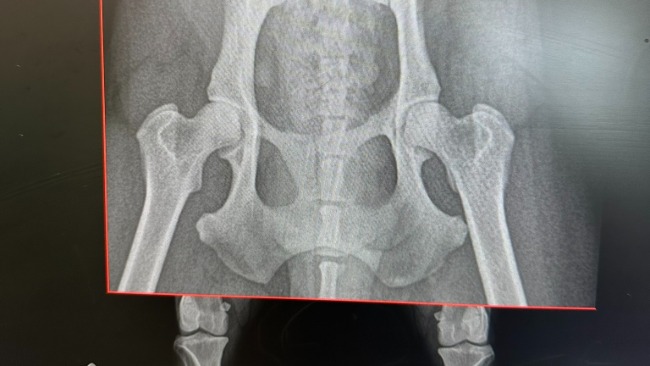

Aria ma pęknięcia w stawie biodrowo-krzyżowym oraz spojeniu łonowym i nie potrafi wstać na tylne łapki, choć dzielnie próbuje podnieść się na przednich. Jest bardzo obolała, ale mimo cierpienia nie straciła ufności do człowieka, z początku niepewnie, ale pozwoliła zrobić sobie wszystkie badania. Najprawdopodobniej przeleżała kilka dni w trawie przy drodze, przykryta zielskiem i odpadami. Jej ciało jest pokryte licznymi zaognionymi ranami, pełne kleszczy i pcheł, a sierść sfilcowana… Nie wyobrażamy sobie jaki to musi być ból…

W tej chwili Aria była tylko u weterynarza pierwszego kontaktu, a w przyszłym tygodniu czeka ją konsultacja ortopedyczna. Wiemy, że będzie potrzebowała rehabilitacji, a jeśli okaże się konieczna operacja złamania, koszty mogą wzrosnąć…To młodziutka, przeurocza sunia, która dopiero zaczyna życie – nie pozwólmy, żeby skończyło się ono na poboczu drogi.